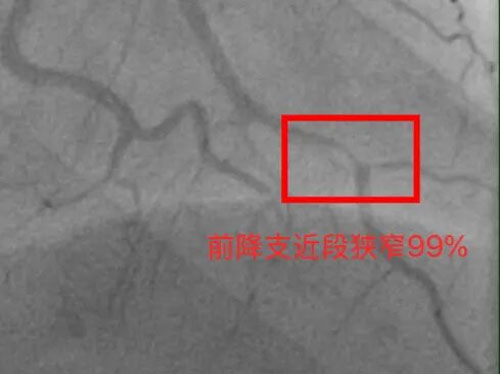

时间就是心肌,时间就是生命。在与家属充分沟通后,心内科团队立即启动导管室,冠脉造影显示:前降支近段狭窄99%——这是心脏重要的血管之一,几近闭塞。

考虑到年轻患者、小血管病变等情况,心内科团队采用了药物球囊,将带有药物的球囊送至狭窄处,在扩张血管的同时释放药物,开通了血管,血流恢复通畅。